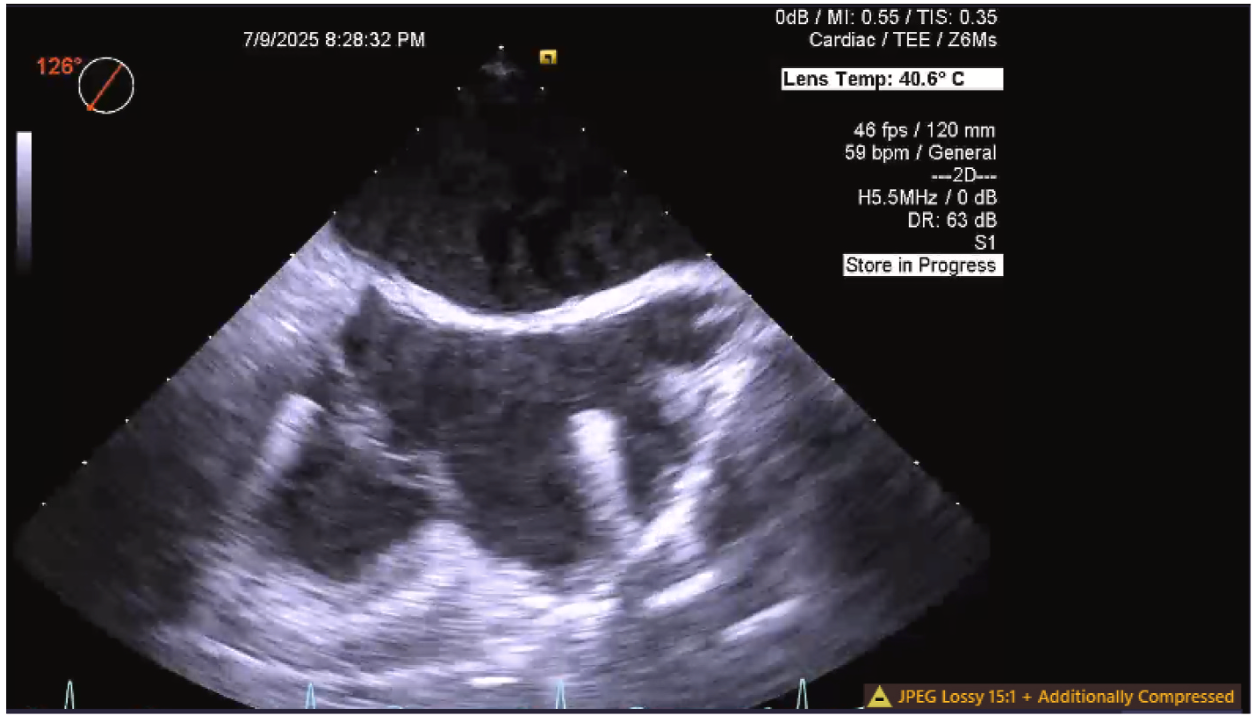

· 患者完成术前放射学成像检查(图1),并成功通过右侧颈内静脉路径植入AVEIR™ DR双腔无导线起搏器(图2),手术过程无任何并发症发生。

图2 心房无导线起搏器植入术中经食管超声成像

· 植入过程需注意尽量减少导管调弯,因为穿过三尖瓣后,过度调弯可能导致导管向前指向右心室游离壁;经食管超声心动图(TEE)用于辅助引导导管穿过三尖瓣,并协助指导低位间隔部植入操作;